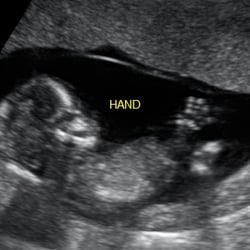

Baby ultrasound clinic is an independent private company that offers 2d3d4d scans with an option of HD live. The Baby Ultrasound Clinic is a pregnancy and ultrasound clinic offering expectant parents the opportunity to see their baby in the womb. Baby ultrasound clinic currently operate from eight locations Bolton Huddersfield MacclesfieldChester Blackpool Stockport Wakefield Prestatyn.

The clinic offers 2D and 3D gender scans from 16 weeks as well as 4D packages that can include DVDs colour prints keyrings and magnets. Growth Report and Estimated weight of baby. After not being able to attend any scans with my partner due to covid first baby too we booked in at the Bolton branch.

From and Early scan - determines pregnancy viability through to a 4D bonding scan - that not only shows you an accurate picture of you baby but also includes a growth report with estimated fetal weight and optional sexing at no extra charge. The Baby Ultrasound Clinic is a pregnancy and ultrasound clinic offering expectant parents the opportunity to see their baby in the womb. We offer in office 3D4D ultrasounds.